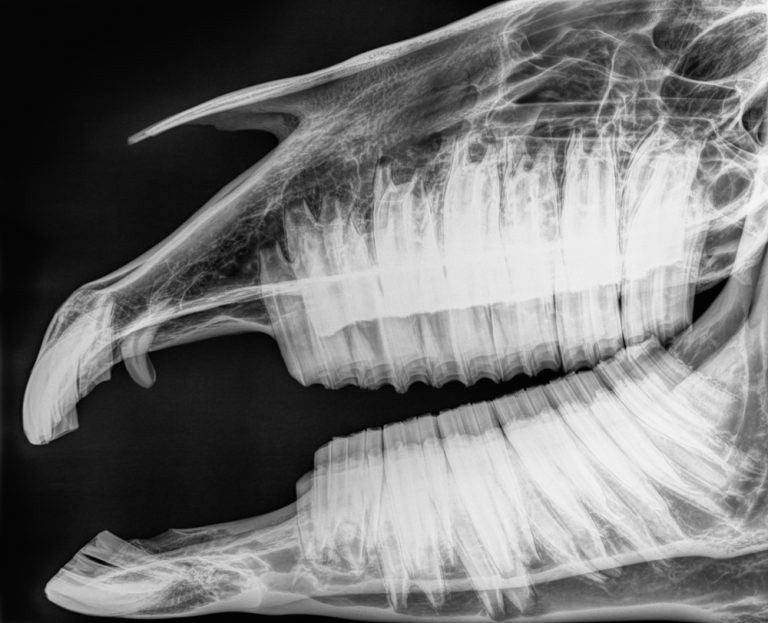

Fredag förmiddag ägnas åt kursens huvudtema ”Hästtandvårdens biologiska grunder” med Rob Pascoe, Torbjörn Lundström och Manfred Stoll som föreläsare om den hypsodonta tanden, parodontium och tandpulpan. Dagen fortsätter med munhåleundersökning – vad är fysiologiskt och vad är patologiskt, sedering och anestesi, därefter föreläsningar om den unga hästen, den äldre hästen och om vad kommunikation med hästägaren är.